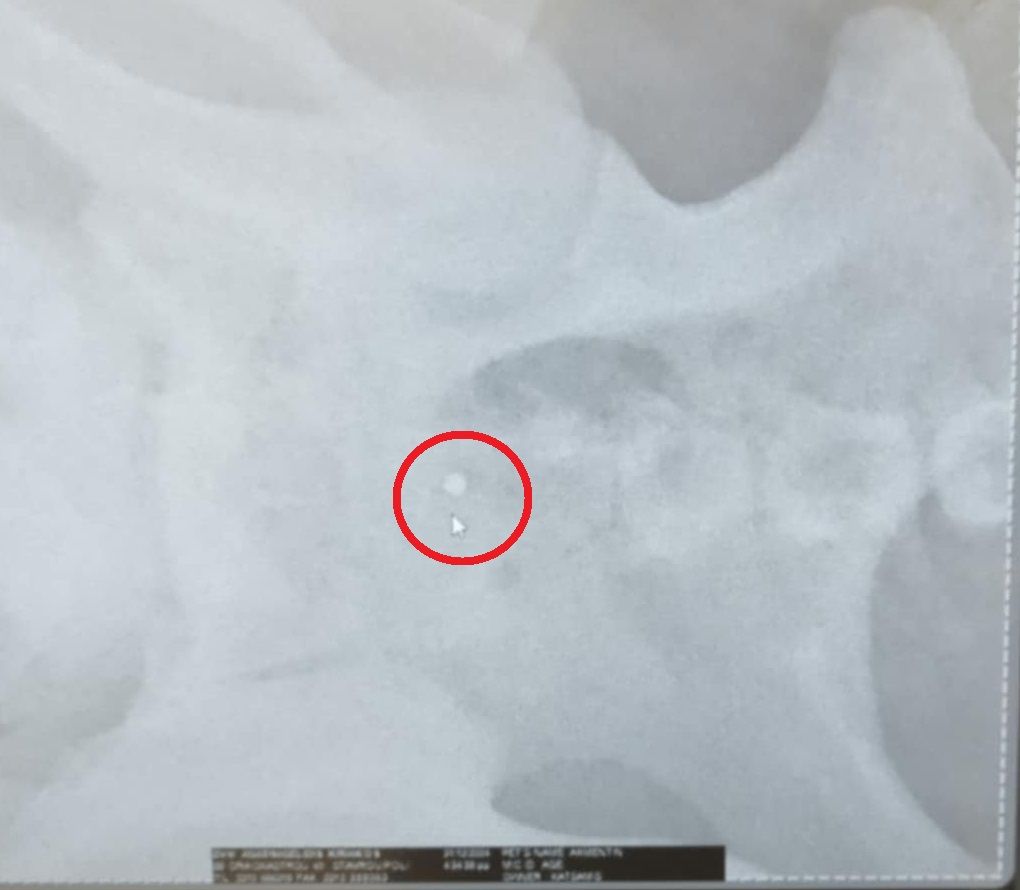

Τελικά οι ακτινογραφίες έδειξαν τι έχει συμβεί. Ο σκύλος είναι πυροβολημένο. Δεκάδες σκάγια εντοπίστηκαν στο σώμα του, στην σπονδυλική στήλη με αποτέλεσμα το ζώο να μην μπορεί όχι μόνο να κινηθεί αλλά και να αφοδεύσει με αποτέλεσμα στο έντερο να έχουν συσσωρευθεί κόπρανα.

Η Ευτυχία Πουρνάρα με αφορμή το περιστατικό επισήμανε τα εξής στις 3 Ιανουαρίου: «ΦΙΛΟΙ ΜΟΥ ΒΟΗΘΗΣΤΕ ΑΥΤΟ ΤΟ ΠΛΑΣΜΑ ΝΑ ΓΙΝΕΙ ΚΑΛΑ ΓΙΑΤΙ ΕΝΩ ΜΟΥ ΕΙΠΑΝ ΠΡΕΠΕΙ ΝΑ ΤΟ ΧΤΥΠΗΣΕ ΑΥΤΟΚΙΝΗΤΟ  ΣΥΓΚΛΟΝΙΣΤΙΚΑ ΟΤΑΝ ΟΙ ΑΚΤΙΝΟΓΡΑΦΙΕΣ ΔΕΙΞΑΝ ΟΤΙ ΤΟ ΚΟΡΜΑΚΙ ΤΟΥ ΣΚΥΛΑΚΟΥ ΕΙΤΑΝ ΓΕΜΑΤΟ ΣΚΑΓΙΑ ΔΙΑΣΠΟΡΑΣ ΕΝΑ ΤΟ ΒΡΕΙΚΕ ΣΤΗΝ ΣΠΟΝΔΥΛΙΚΗ ΣΤΥΛΗ Ο ΓΙΑΤΡΟΣ ΜΟΥ ΚΥΡΙΟΣ ΚΑΡΑΜΗΤΡΟΣ ΜΟΥ ΕΔΩΣΕ ΑΓΩΓΗ  ΤΟ ΖΩΟ ΔΕΝ ΜΠΟΡΟΥΣΕ ΝΑ ΑΦΟΔΕΥΣΗ ΚΑΙ ΠΡΙΣΤΗΚΕ ΚΑΝΟΥΜΕ ΑΓΩΝΑ ΝΑ ΤΟ ΒΟΗΘΗΣΟΥΜΕ ΤΟ ΚΑΛΟ ΕΙΝΑΙ ΟΤΙ ΑΙΣΘΑΝΕΤΑΙ ΤΑ ΠΟΔΑΡΑΚΙΑ ΤΟΥ ΘΑ ΣΑΣ ΠΩ ΝΕΟΤΕΡΑ ΤΟ ΚΑΘΑΡΜΑ ΠΟΥ ΤΟ ΠΥΡΟΒΟΛΗΣΕ  ΕΥΧΩΜΕ ΑΥΤΟ ΠΟΥ ΕΚΑΝΕ ΝΑ ΤΟ ΒΡΕΙ ΜΠΡΟΣΤΑ ΤΟΥ ΜΗΝ ΞΕΧΝΑΤΕ ΒΟΗΘΗΣΤΕ  ΕΧΩ ΑΓΩΝΑ ΜΠΡΟΣΤΑ ΜΟΥ ΓΙΑ ΝΑ ΣΩΘΕΙ ΣΤΕΙΛΤΕ ΜΗΝΝΥΜΑ ΣΤΟ ΜΕΣΣΕΝΤΖΕΡ  ΕΥΧΑΡΙΣΤΩ ΠΟΛΥ ΤΗΛ 6946348888 ΚΙΛΚΙΣ».